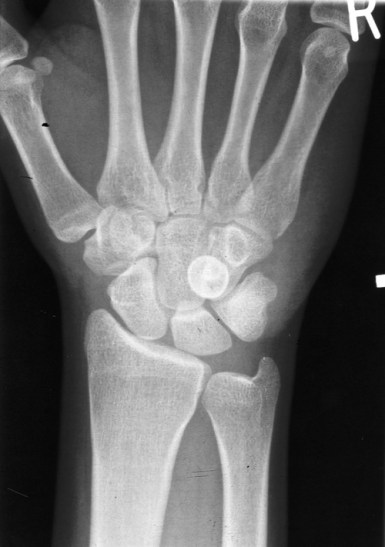

- If you hit the reef hard the pain may distract you from sprains and joint damage. Be suspicious of pain in the joints either side of the injury.

- Remember its possible to damage nerves and arteries beneath wounds.

- If the coral cut is deep and potentially entering a joint space you should go to a hospital for surgical cleaning.